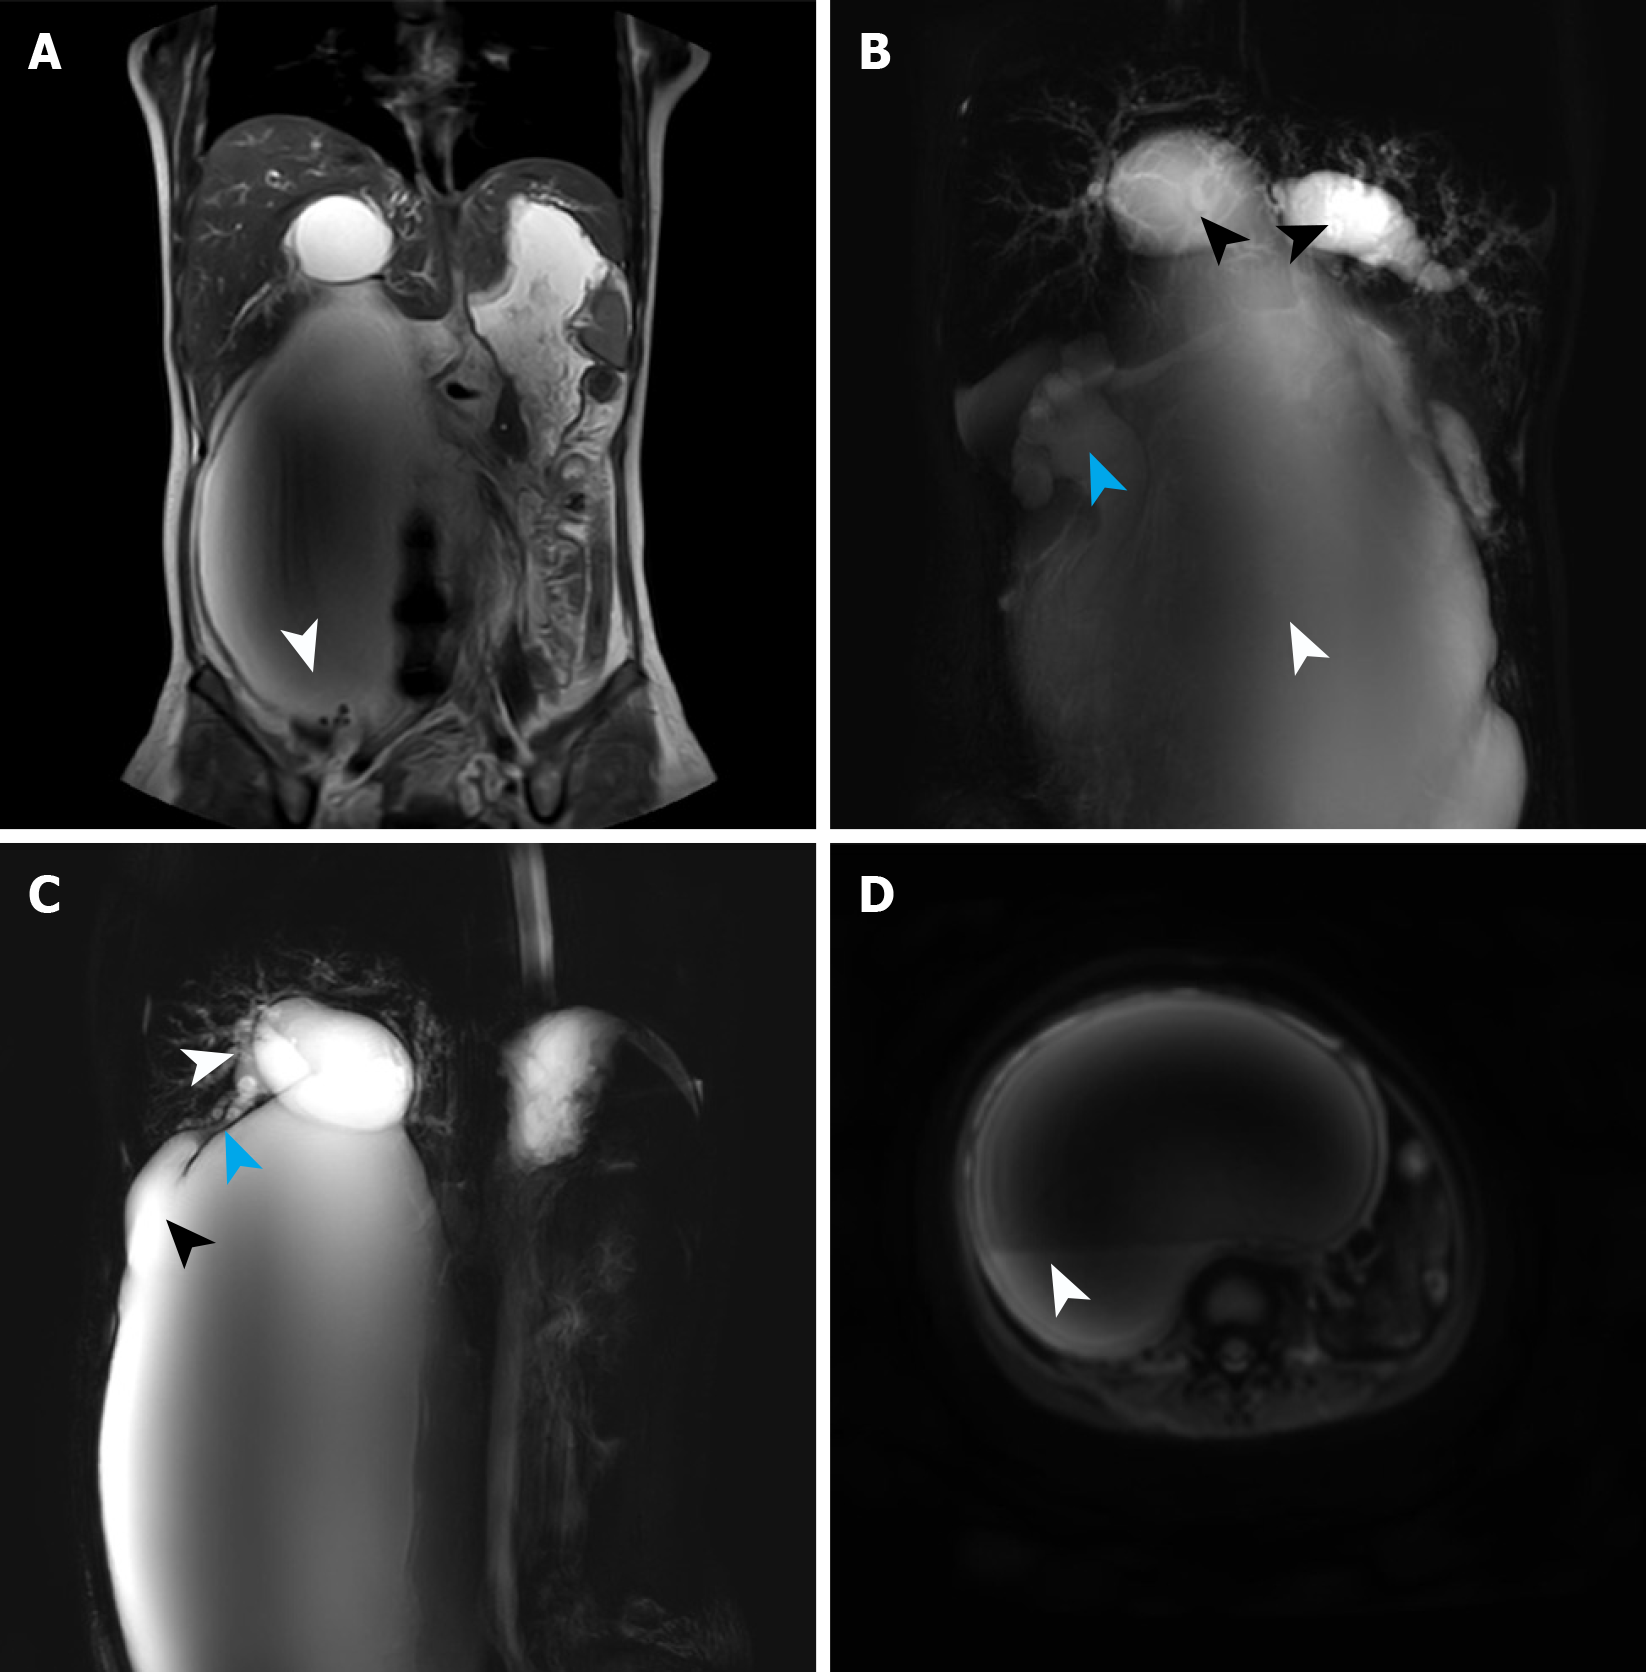

Upon admission, the patient underwent magnetic resonance imaging and magnetic resonance cholangiopancreatography (MRCP), which identified a giant cystic lesion in the abdominal cavity, measuring approximately 338.05 mm × 194.66 mm × 131.61 mm (Figure 1). Multiple calculi were observed at the cyst base (Figure 2A). Moreover, MRCP confirmed cystic dilatation of the common bile duct and intrahepatic biliary ducts, accompanied with hydronephrotic dilatation of the renal pelvis (Figure 2B), which was caused by ureteral compression by the cyst. The gallbladder was atrophic as a function of impaired bile storage and secretory function (Figure 2C). Diffusion-weighted imaging sequences (Figure 2D) revealed layering of the cystic contents, suggesting biliary sludge sedimentation. Following the classification guideline of Todani et al[8], the choledochal cysts were classified into five types. Type I is more prevalent in pediatric populations, whereas type IV (subclassified as IV-A in this case) is frequent among adults[9]. The patient in this case was diagnosed with a type IV-A choledochal cyst.